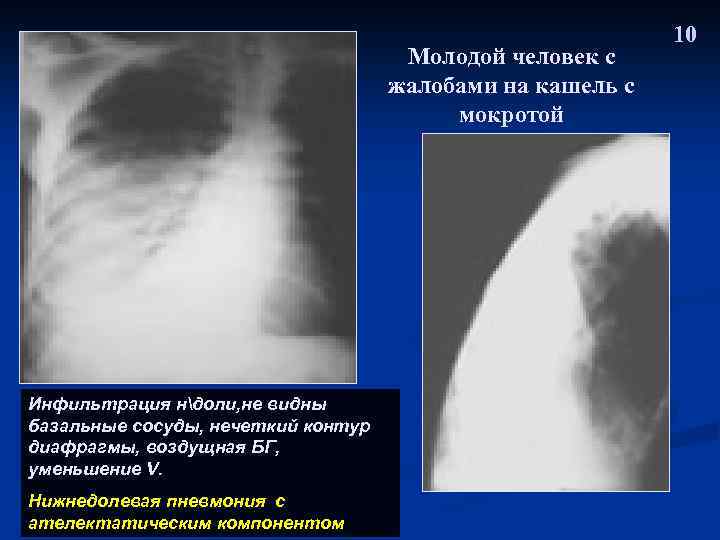

Молодой человек с жалобами на кашель с мокротой Инфильтрация ндоли, не видны базальные сосуды, нечеткий контур диафрагмы, воздущная БГ, уменьшение V. Нижнедолевая пневмония с ателектатическим компонентом 10